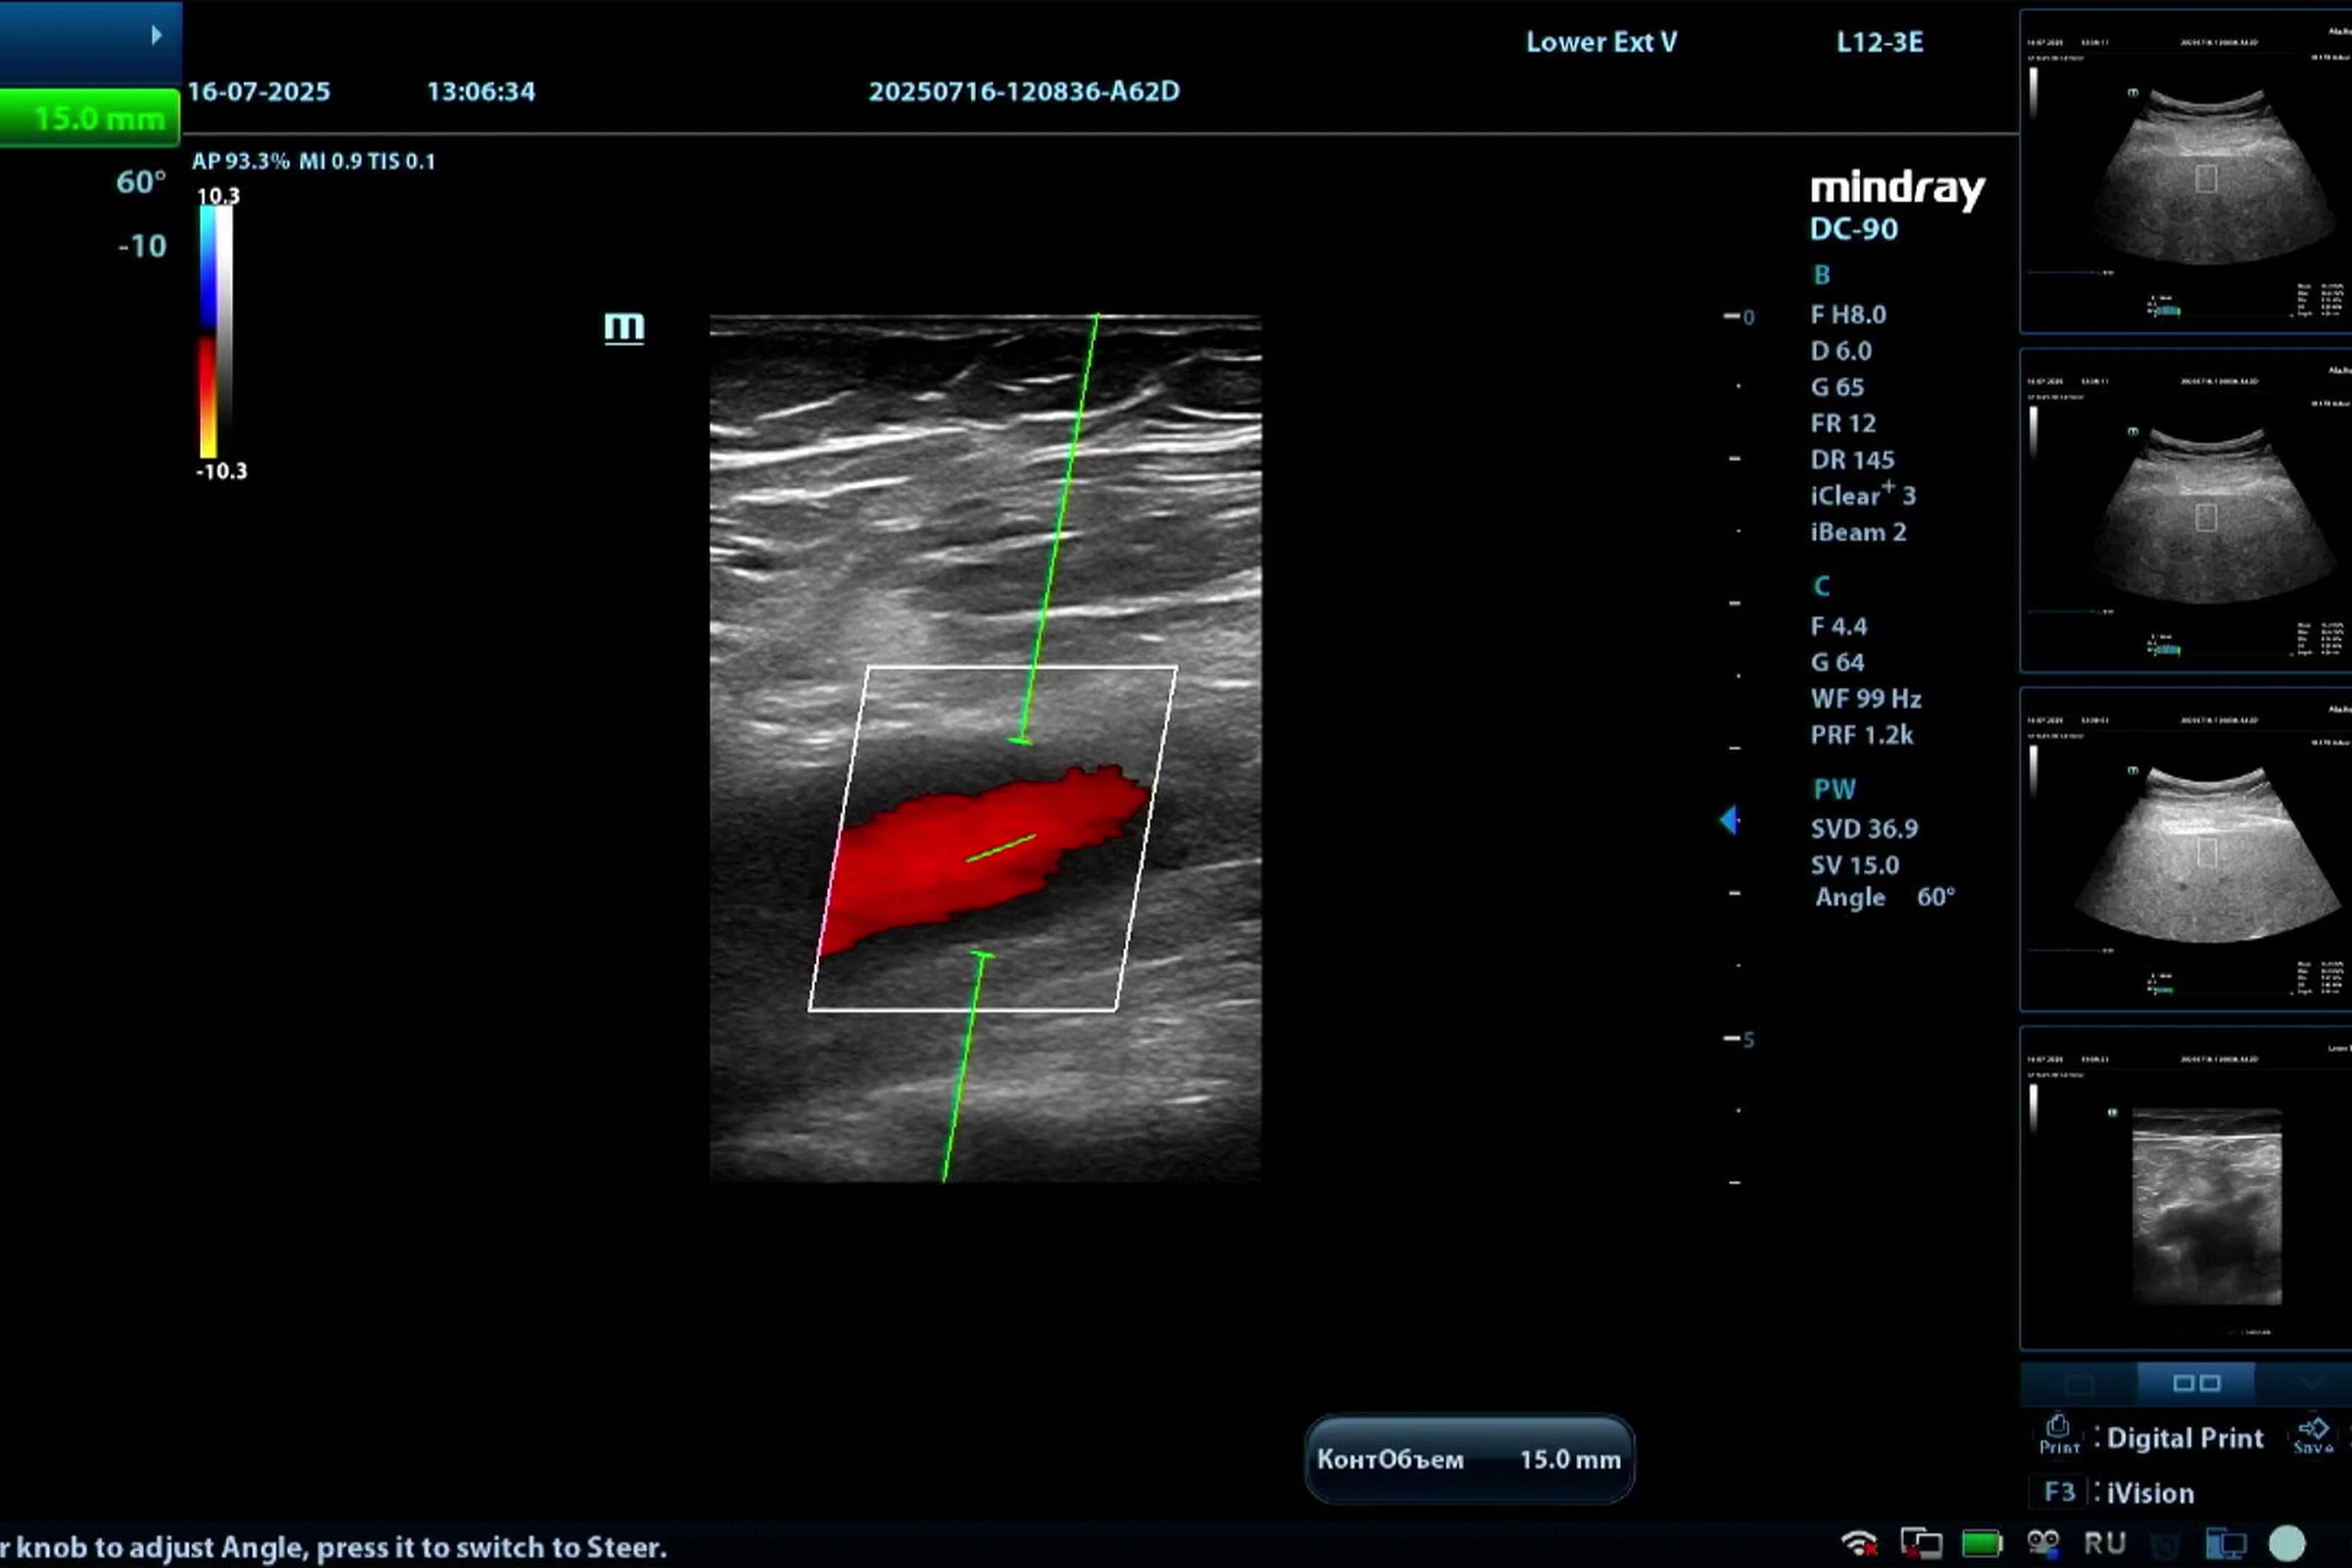

Медицинское оборудование для ультразвуковой диагностики